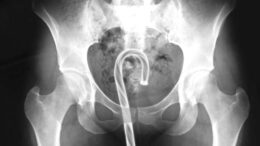

OMG, Defector lists all the objects we got stuck in our rectums last year

2020 has been a year of reflection. A year of boredom. A year of looking… INWARD. Check out a comprehensive list of all the things…